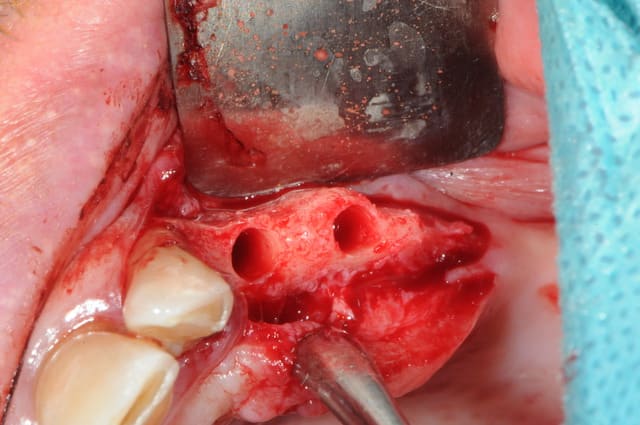

en fait le boulot n'est pas complétement terminé car après les implants sur 35/36 qui sont ici visibles je doit corriger la courbe occlusale en m'occupant de 43à46

en fait, c'est la crête de 23à26; l'image est inversée par le miroire.

mais tu as raison et j'en ai bavé et pas seulement à postériori mais aussi pendant l'effort...

expansion +++ à l'ostéotome